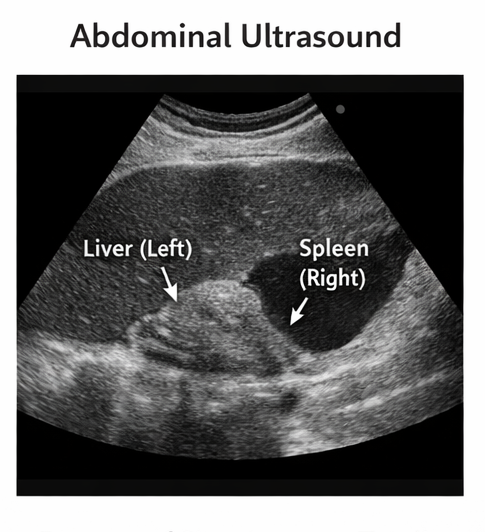

Ultrasound Abdomen

Abdominal ultrasonography demonstrated mirror-image arrangement of abdominal viscera. The liver and gallbladder were located in the left upper abdomen, while the spleen and stomach were located on the right side.